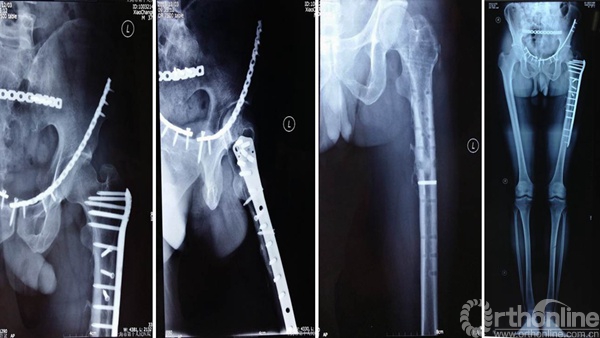

进针点和力线很难把握,即使应用很巧妙的复位技术获得了术后很好的力线,避免了髋内翻,但如此大块的骨块劈裂游离不处理,会存在退钉和骨不连或者髓内钉断裂的风险。

钱XX,女,43岁

术后